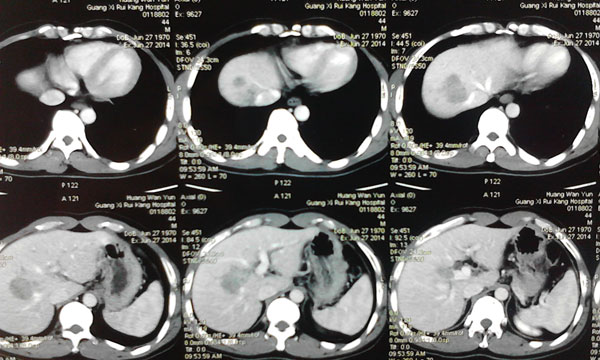

患者确诊为原发性肝癌,肿瘤位于肝脏的ⅦⅧ段,侵犯肝右静脉,与肝中静脉关系密切,必须行右半肝全切除,残留肝体积需达到标准肝体积的40%左右才能保证术后肝功能正常,而患者的残留肝脏体积仅占标准肝体积的30%,传统上认为达不到手术切除的要求。韦杨年主任决定采用世界肝脏外科革命性的二步肝切除技术。

7月4日卫生部肝胆肠中心的李年丰教授和我院肝胆外科主任韦杨年副教授及其团队,为患者实施采用第1 步腹腔镜下肝脏离断和门静脉右支结扎,以此减少右侧肝的血液供应,同时将左、右半肝劈开分离。

肿瘤的位置

肿瘤与肝动脉

肿瘤与肝静脉